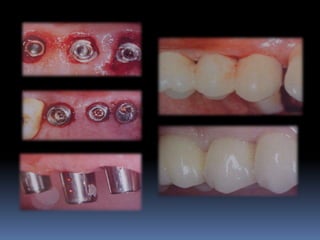

Planejamento em implantodontia

número

Posicionamento

distribuição

tridimensional

Emergência

plataforma

protética

Seleção de plataformas ideais

Distribuição e número dos implantes na arcada